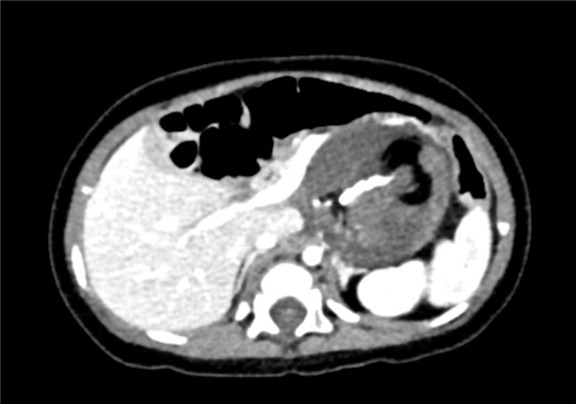

下腹部增强CT示:腹腔巨大占位,考虑畸胎瘤可能性大

术前CT检查:

动脉期